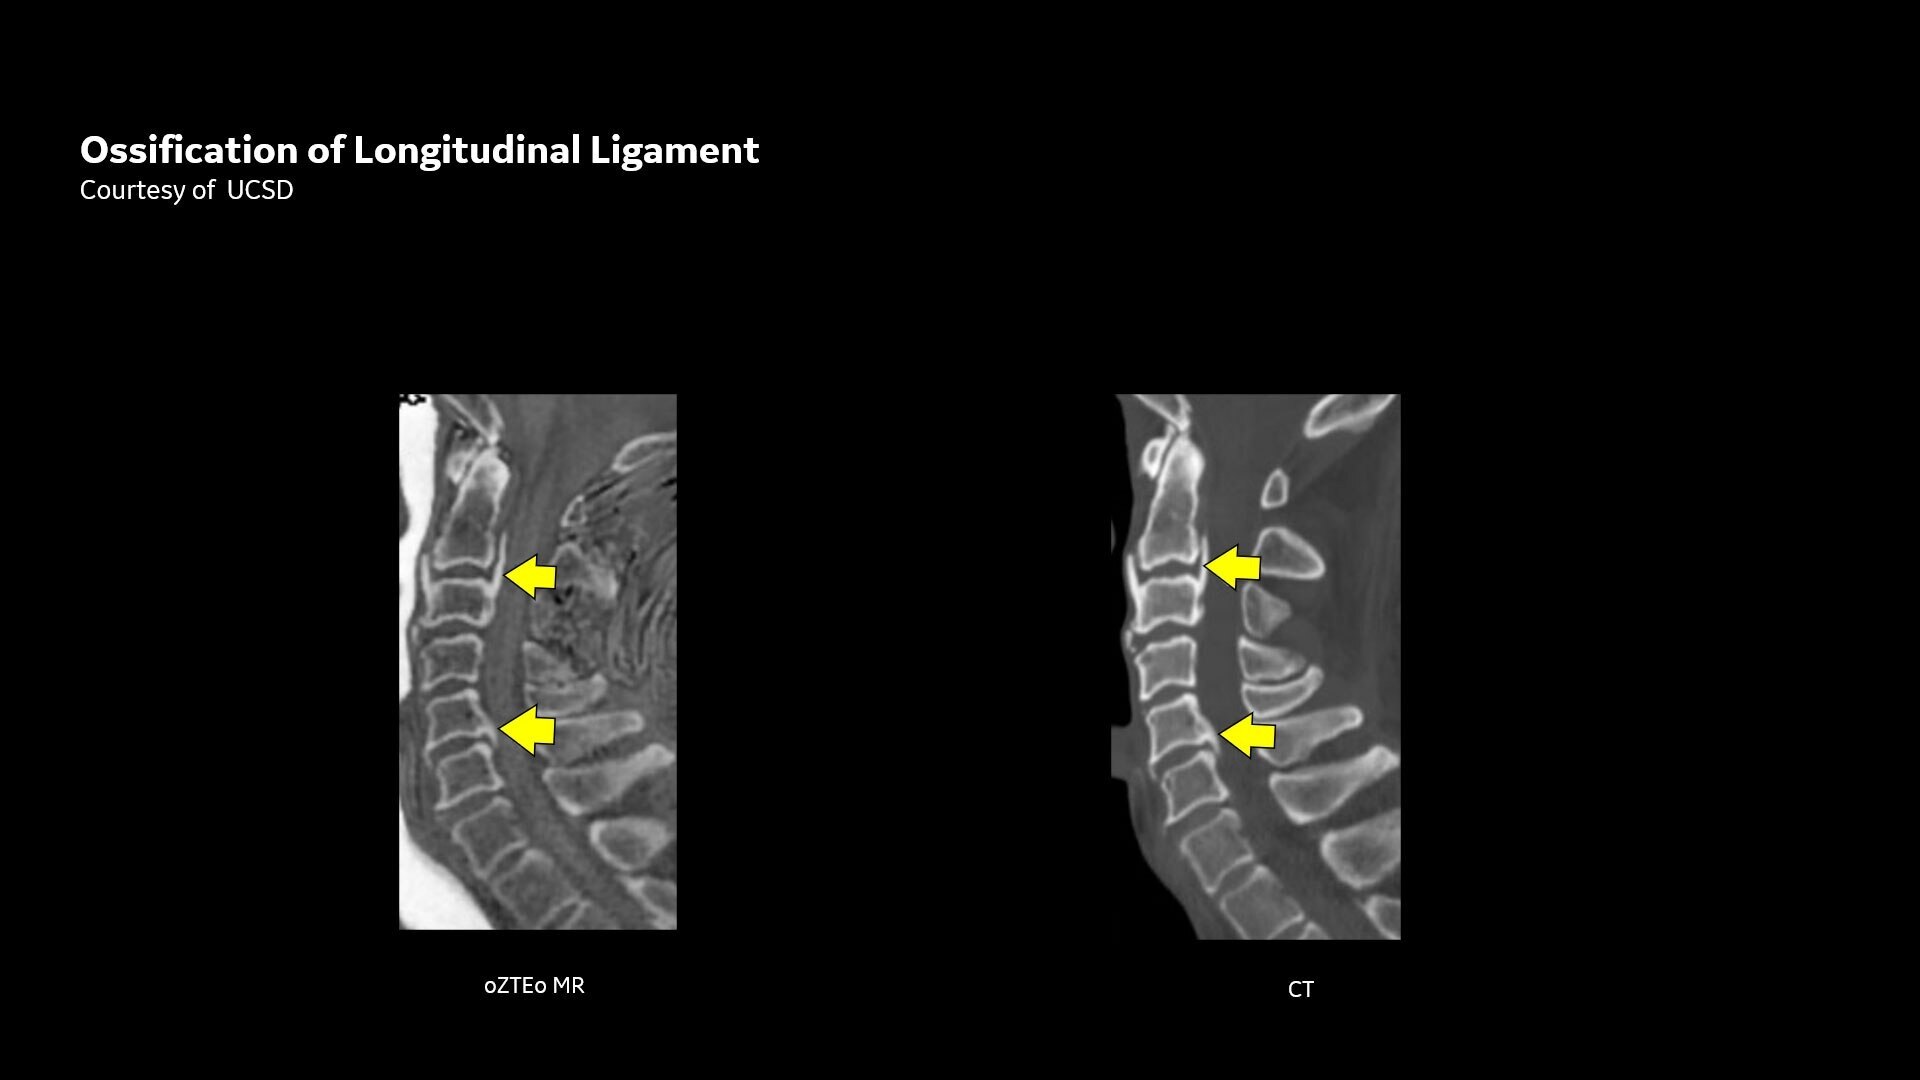

Available for all anatomies without ionizing radiation, oZTEo delivers images of bone morphology, calcification, ossification and fractures. oZTEo complements conventional MR soft tissue exams with perfect co-registration and provides 3D isotropic imaging using a radial ZTE acquisition, with inherent motion insensitivity. Use oZTEo with Volume Illumination for realistic 3D rendering.

CT-like image contrast without ionizing radiation

MR bone imaging provides a CT-like image contrast without ionizing radiation, making it an attractive alternative for pediatric and pregnant patients where ionizing radiation is a concern. In addition, it provides a welcome alternative when longitudinal CTs are required, particularly when low-dose CT systems are unavailable.